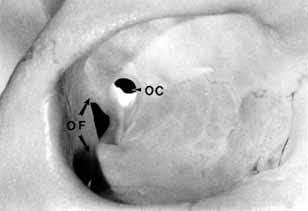

ANATOMY Orbit The orbital apex has two major openings, the orbital fissure and the optic canal (Fig. 1). The orbital fissure is divided into a superior and inferior portion by the tendon of Zinn, the inferior insertion for the tendinous anulus of Zinn (Fig. 2).1,4 (The anulus of Zinn is completed by the origins of the rectus muscles and the superior tendon of Lockwood.) Structures emanating through the optic canal (the optic nerve, ophthalmic artery, and orbital sympathetic nerves) as well as some structures coursing through the superior orbital fissure (the superior and inferior branches of the oculomotor nerve (cranial nerve III), the abducens nerve (cranial nerve VI) and the nasociliary branch of the ophthalmic division (cranial nerve V1) of the trigeminal nerve pass through the anulus of Zinn.